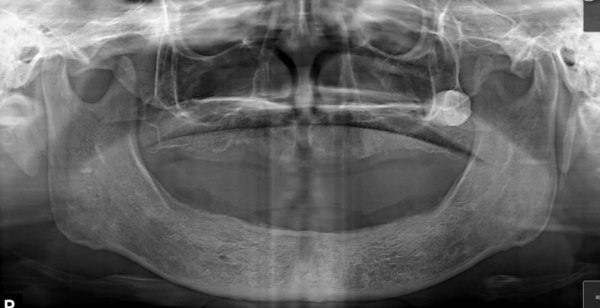

CBCT三维立体全景影像片 缺牙严重

在做种植牙前,王阿姨带了很长一段时间的活动假牙,然而带的时间久了,一个个牙龈很容易发炎,还很疼。